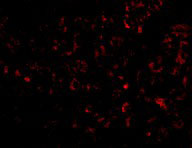

Immunofluorescence of Albumin in Human Liver cells with Albumin antibody at 20 μg/mL. |